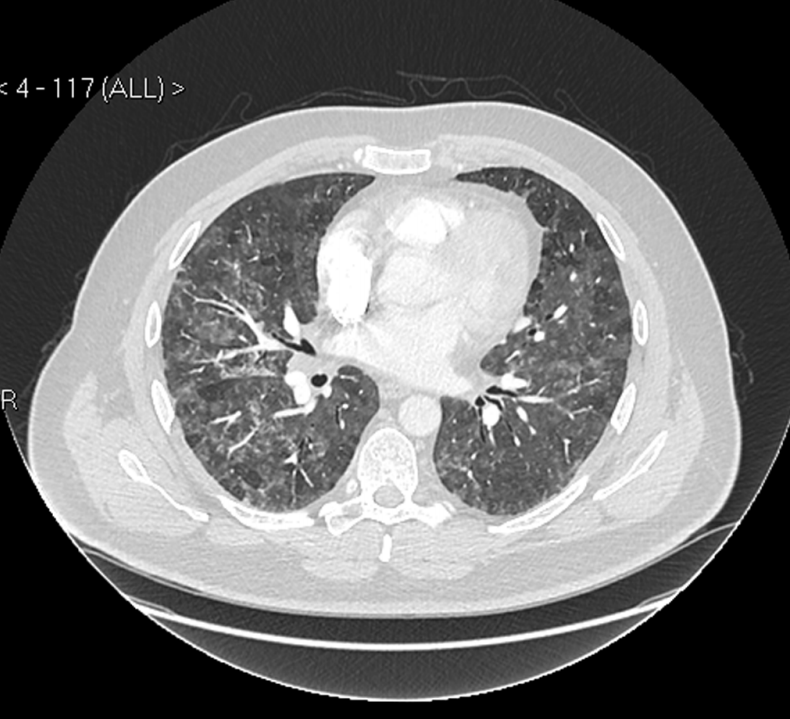

From www.researchgate.net

Chronic HSP caused by feather pillows. Notes Male, 67 years of age Feather Pillows Lung Disease When a patient reported being so short of breath he could barely walk, many physicians were stumped. It took a nosy doctor. Breathing in this dust triggers a reaction in the body, causing lung inflammation and difficulty breathing. Fdl is caused by inhalation of organic. In 2016, taylor developed “feather duvet lung,” a form of hypersensitivity pneumonitis, or “bird fancier’s. Feather Pillows Lung Disease.

Interstitial Lung Disease Photograph by K H Fung/science Photo Library Feather Pillows Lung Disease When a patient reported being so short of breath he could barely walk, many physicians were stumped. Feather duvet lung or hypersensitivity pneumonitis, is a lung problem caused by sensitivity to antigen from feathers in duvets and pillows filled with duck or goose feathers. In 2016, taylor developed “feather duvet lung,” a form of hypersensitivity pneumonitis, or “bird fancier’s lung,”. Feather Pillows Lung Disease.

Obstructive Lung Disease Photograph by John Bavosi Fine Art America Feather Pillows Lung Disease Feather duvet lung or hypersensitivity pneumonitis, is a lung problem caused by sensitivity to antigen from feathers in duvets and pillows filled with duck or goose feathers. Feather duvet lung (fdl), is an immunologically mediated form of hypersensitivity pneumonitis (hp), also sometimes called extrinsic allergic alveolitis. Feather duvet lung or hypersensitivity pneumonitis, is a lung problem caused by sensitivity to. Feather Pillows Lung Disease.